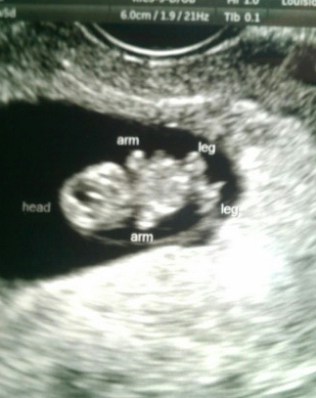

| Hello, THREE! |

ONE knows that “Mommy has a baby in her tummy” and he seems excited about becoming a big brother again. He gently pats my stomach and talks to it.

Today I am thankful for the things life has thrown at us, because through those experiences we have learned that as long as we have our health and each other, we’re good. We have been blessed with two beautiful children and now we have another one on the way … sometimes when I sit back and let that information sink in, I get overwhelmed because it’s yet another miracle. Three healthy children. That’s amazing.